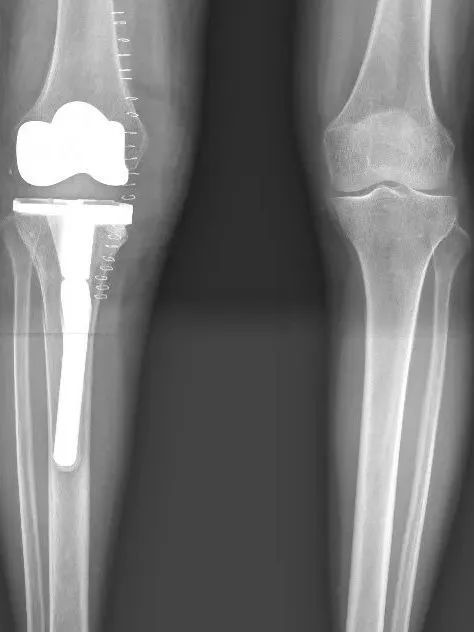

医生告诉她,干骺端骨质严重破坏,关节稳定性丧失,已发展为安德森Ⅱa型骨缺损。传统抗结核药物、常规清创术及常规关节置换手术难以恢复关节功能,日常生活将会受到极大影响。

“别轻易放弃,我们与你一起渡过难关!”骨科沈健主任医师团队仔细研究鲍女士的情况后,决定为其实施全膝关节置换术。

据主刀医生沈健主任医师介绍,膝关节结核的全关节置换术技术难度大,既要彻底清除结核病灶防止死灰复燃,又要在被严重破坏的骨质结构中重建稳定的关节系统,难度堪比“在废墟上重建宫殿”。

安德森分型Ⅱa型即为膝关节结核的晚期阶段之一,其特点是明确的骨质破坏和关节结构改变,但尚未合并广泛脓肿或窦道形成。

安德森分型是国际上广泛使用的骨缺损分型系统,膝关节结核患者多伴有骨质缺损,其中Ila型主要表现为:

➤单侧髁部骨缺损;

➤关节间隙狭窄或消失;

➤关节周围可能出现局限性脓肿。